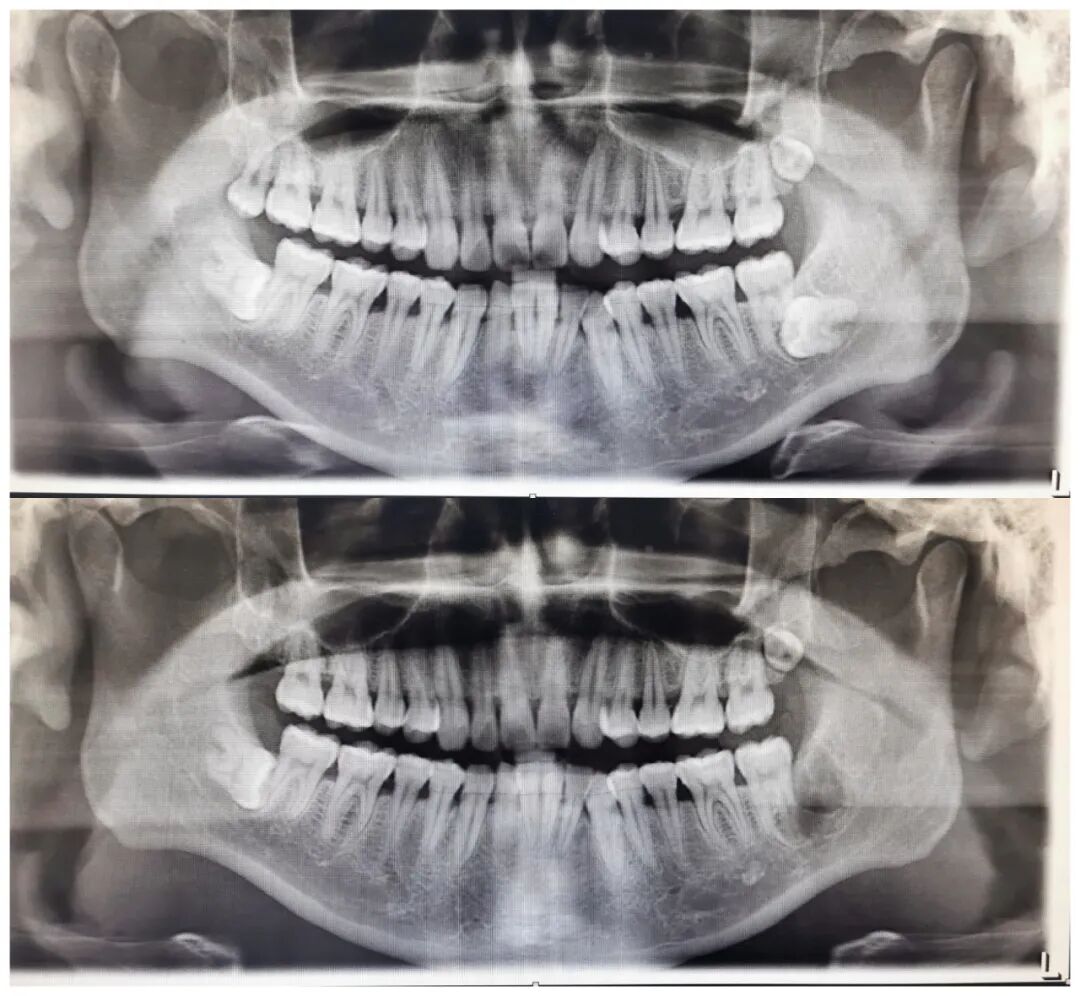

联勤保障部队第九二四医院口腔科,于2006年10月10日开始正式挂牌成立。科室目前拥有口腔综合治疗台16台及先进的显微根管治疗系统、笑气镇静系统、卡瓦种植牙系统、曲面断层摄片系统、高频电刀、激光微波等治疗设备。严格规范的消毒流程设计、消毒过程控制加上原装德国进口的消毒灭菌设备及全自动清洗系统,坚决杜绝了口腔诊疗的各种交叉感染的发生。科室采用澳大利亚昆士兰(Queensland)牙科诊疗模式,设置了宽敞明亮的独立诊室以及全封闭的方式接诊,充分保证每一个患者的隐私。科室每年门诊量约3.5万人次,病房年收容量约300人次 、手术量达3500余例 。

口腔颌面外科(如微创拔牙、种植牙、阻生牙等复杂牙齿拔除、颌面部肿瘤、外伤颌骨骨折、颌面部感染、唇腭裂等)。

1、微创拔牙技术:先进的微创理念,采用特殊的器械和方法,以最小的创伤拔除患牙。相比传统拔牙,微创拔牙具有疼痛小、恢复快、并发症少等优势。

2、种植牙技术:通过植入人工牙根来恢复牙齿功能和美观。种植牙不仅外观自然,而且功能上与真牙相近,被广泛应用于牙齿缺失的修复。种植牙的优点包括稳固性好、使用寿命长、舒适度高等,是现代口腔医学的重要成果之一。